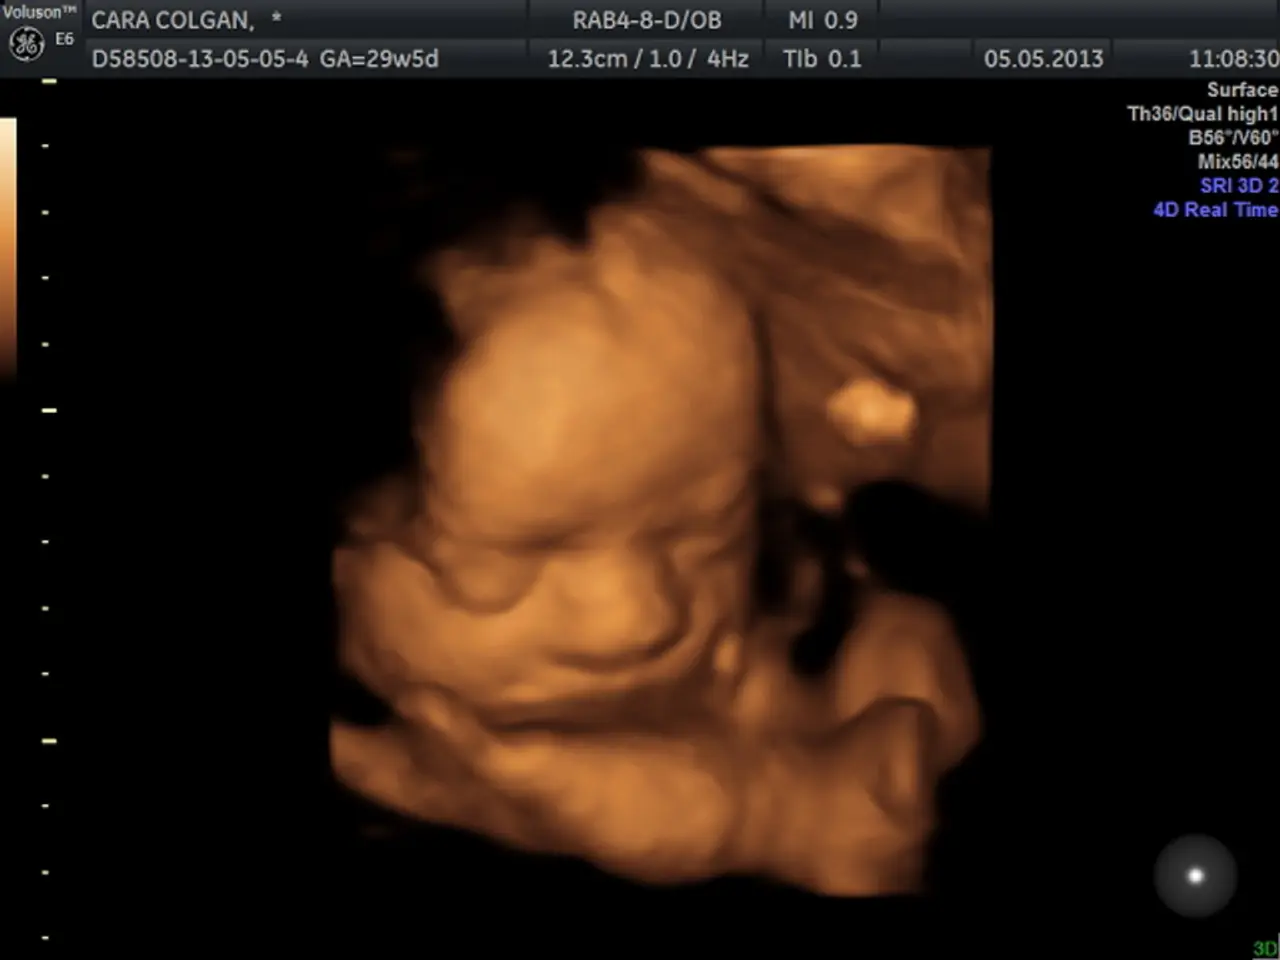

In this image we can see a screen with text and image of a baby.

In Sweden, a baby girl developed a 'micropenis' and other male characteristics after lying on her father's bare chest, which had testosterone gel applied due to his hypogonadism. The baby's clitoris elongated, and her labia fused, resembling male genitalia. The condition reversed once her father stopped using the gel and the exposure ceased. A Swedish doctor has seen at least half a dozen similar cases involving young children unintentionally exposed to hormone medication through close contact with a parent. In one case, a 10-year-old boy developed breasts after coming into contact with estrogen cream his mother had been using. To avoid such incidents, it is advised to wash hands thoroughly after applying hormone gels and to rinse the treated area before any skin-to-skin contact.